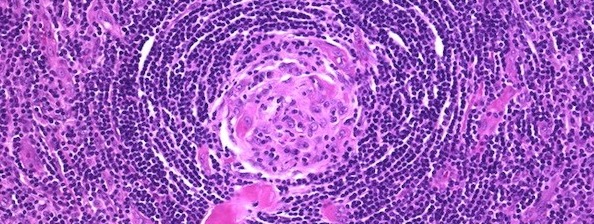

더불어 영상검사를 통해 몸 어디에서든 1cm 이상의 림프절 비대(1개면 단발성 캐슬만병, 2개 이상이면 다발성 캐슬만병)가 확인돼야 한다. 동시에 림프절 조직검사에서 양파껍질 같이 생긴 특수 모양의 병리조직(사진)이 확인돼야 한다.

면역세포가 중심 축에 쭉 모여 있는 모양인데, 회오리 모양의 중심에서 인터루킨 6를 만드는 것이다. 림프절 비대가 있어도 회오리 모양의 병리조직이 없으면 캐슬만병이 아니다.